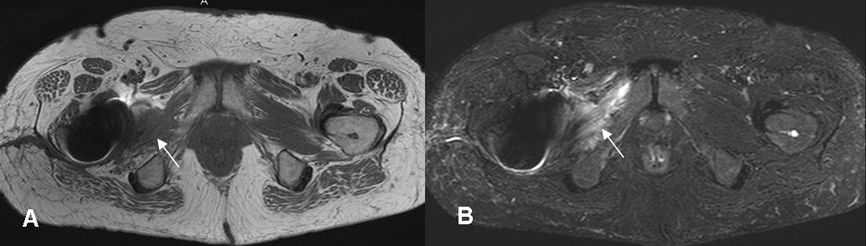

Fig 23. Miositis.

A: RM axial en T1 y B: RM axial en STIR. Cambios inflamatorios en los músculos pectíneo y obturador externo, los cuales son hipointensos en T1, hiperintensos en STIR y rodeados por líquido, por miosistis. Hay prótesis en la cadera, que produce artefactos.